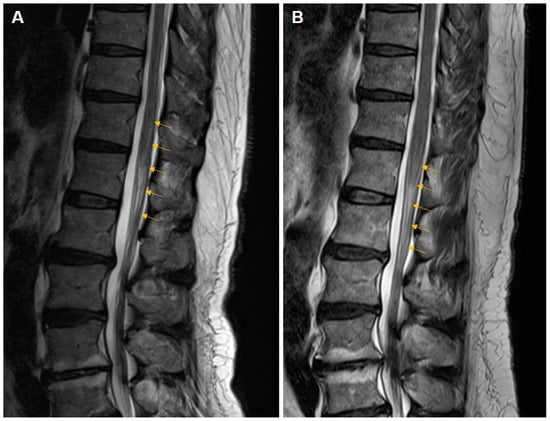

Thoracolumbar spinal MRI taken on the fourth day of symptom onset showed a diffuse, longitudinal, high-signal lesion with mild enlargement of the spinal cord from T12 to L1 (Figure 1A). Subtle enhancement was observed in the lesions following administration of gadolinium–diethyltriaminepentaacetic acid. T2-weighted and fluid-attenuated inversion recovery (FLAIR) images showed hyperintense lesions and subtle enhancement in the conus medullaris and proximal cauda equina.

Eighteen months after the first onset, he visited the outpatient clinic for bilateral lower extremity tingling, numbness, and weakness, which were reportedly similar to the previous symptoms. Significant infection-related symptoms were not specific within three months before the second attack. Sensory deficits were the main complaint and were most severe in the left L5 dermatome. Upper motor neuron signs were observed in both the lower extremities. There were no specific abnormalities on blood tests other than a slightly increased white blood cell count (12.3 × 103 cells/μL). The IgG index was 0.591. Needle electromyography revealed polyphasic and large-amplitude MUAPs with reduced recruitment patterns on the left L5 and bilateral S1 myotomes and abnormal spontaneous activities on the left L5 myotome. MRI at the time of the relapse revealed a similar lesion at the level from L1 to L2 (Figure 1B).

Figure 1. Sagittal T2-weighted views from thoracolumbar spinal magnetic resonance imaging (MRI). MRI at the first attack showed a diffuse longitudinal high-signal lesion (yellow arrows) with mild enlargement of the spinal cord from T12 to L1 (A). MRI at the recurrent attack revealed a similar lesion from L1 to L2 (B).

In this report, we outline a clinically intricate instance of ADEM that primarily affected the spinal cord, but exhibited concurrent involvement of certain spinal nerve roots. Our assessment attributed this condition to spinal ADEM. During the 3-week progressive phase of the disease, the patient exhibited partial electrophysiological regression following immunosuppressive treatment within one week of symptom onset. A subsequent follow-up 18 months after disease onset revealed a relapse in symptomatology. Serial electrodiagnostic studies enabled the estimation of spatiotemporal changes in lesion progression. The lesions were predominantly localized in the distal conus and cauda equina, progressed toward the proximal conus in tandem with symptom evolution, and lacked clear lateralization. Primarily, demyelination-related impairments prevail and are occasionally accompanied by axonal damage in severe cases. Evident alterations in the S1 dermatomyotome include both latency delays and amplitude decreases. Notably, there was a latency delay in the subsequently affected L5 dermatomyotome; however, no substantial decrease in amplitude was observed. The MRI findings were consistent with the electrodiagnostic outcomes, demonstrating more proximal signal alterations during the initial episode and showing changes below one vertebral level during the relapse. The precise nature of these signals, and whether they reflect residual lesions from the initial inflammation or new manifestations due to recurrence, remains uncertain. Notably, the electrodiagnostic test revealed no myotomal expansion or increased abundance of abnormal spontaneous activity.